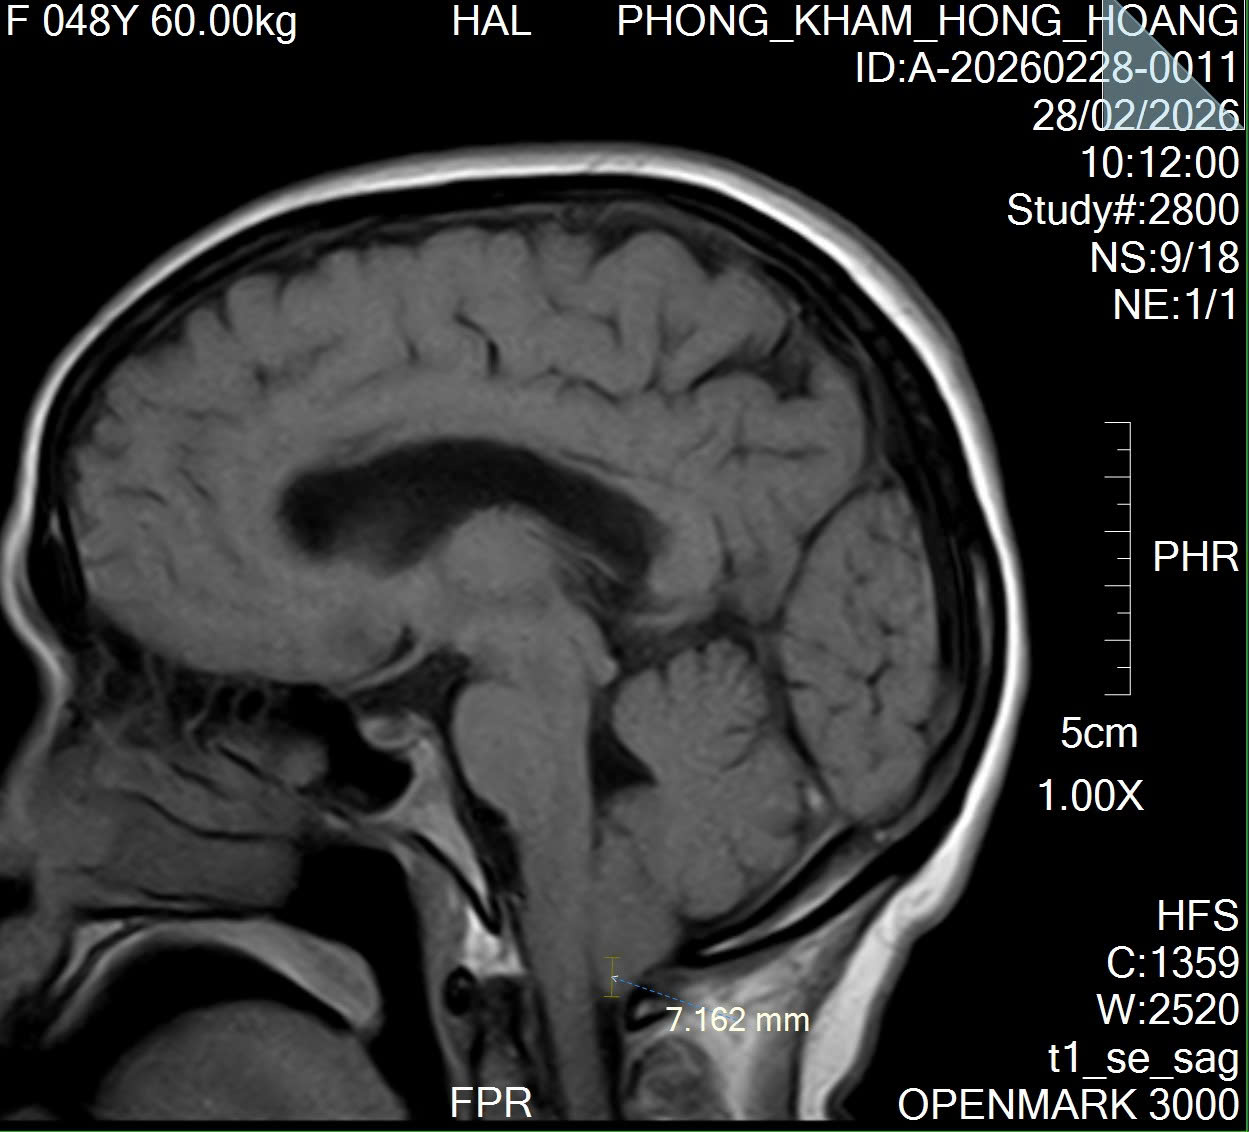

PHÁT HIỆN DỊ TẬT CHIARI NHỜ CHỤP CỘNG HƯỞNG TỪ SỌ NÃO (MRI)

Dị tật Chiari là một bất thường bẩm sinh ở vùng não – cột sống, trong đó một phần của tiểu não bị tụt xuống qua lỗ chẩm vào ống sống cổ. Tình trạng này có thể gây chèn ép não và tủy sống, dẫn đến n...